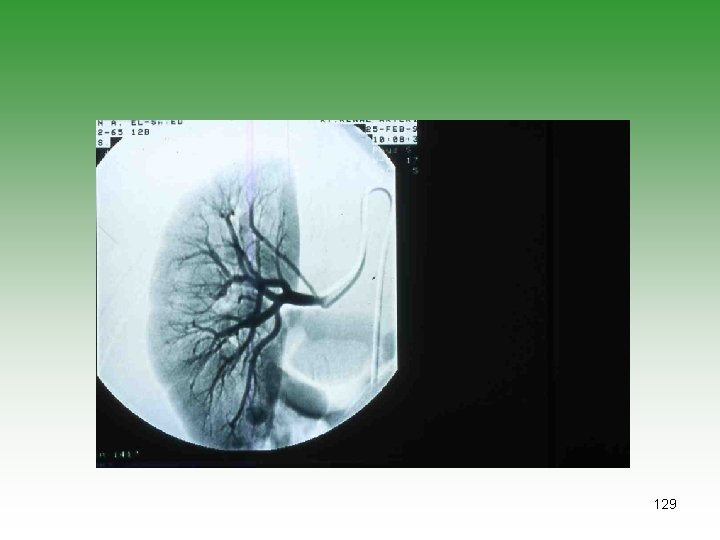

129

- Slides: 129